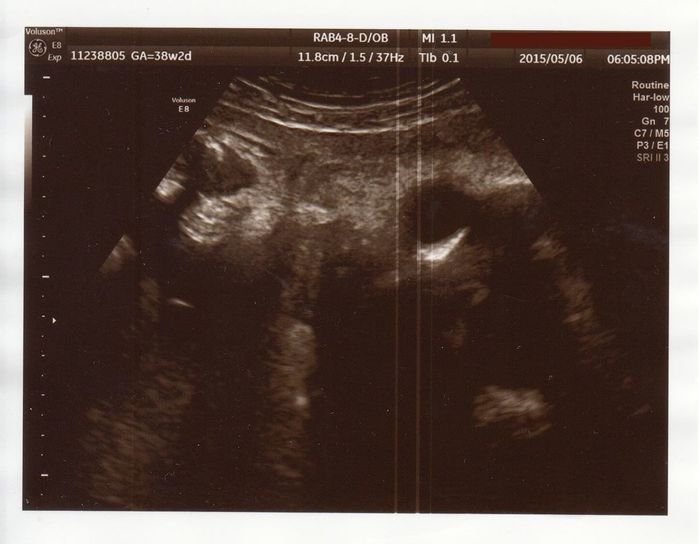

週1で通院、毎回NSTで赤ちゃんのチェック - 妊娠36週目のエコー写真

どこを写したものなのかちょっと分かりにくいですが、顔のアップだと思います。右上の線が頭のラインで、真っ黒な部分が頭です。4月に2人目の子どもが幼稚園に入園。週に一度、自分で車を運転して大学病院の検診に行き、そのたびに、30分ほどNSTを受けました。赤ちゃんの体重が増えない原因は分かりませんでしたが、羊水が普通より少ないと言われました。通うことになった大学病院では、毎回医師が変わり、言うことも少し違うので戸惑ったのを覚えています。